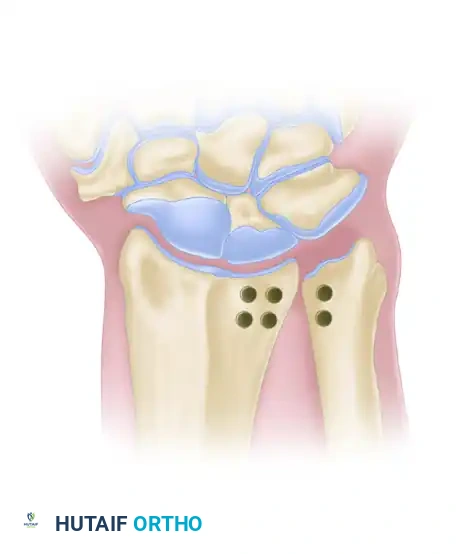

Step 1: Osseous Preparation

* Following exposure of the DRUJ, specific drill holes are created in both the distal radius and the distal ulna.

* Two holes are drilled in the radius (dorsal and volar to the sigmoid notch) and two corresponding holes are drilled in the ulnar neck.

Figure: Location of the transosseous holes drilled in the distal radius and ulna for the Liebolt technique.

Step 2: Tendon Routing

* A robust graft (such as fascia lata or a free tendon) is passed in a figure-of-eight or box configuration through the drill holes.

* This routing mimics the anatomic vectors of the native dorsal and volar radioulnar ligaments.

Figure: Method of passing the tendon graft through the radius and ulna to recreate the radioulnar ligaments.

Step 3: Tensioning and Fixation

* The joint is reduced and held in neutral rotation.

* The graft is tensioned and sutured to itself. The stability of the DRUJ is tested through a full range of pronation and supination before final closure.

Figure: Final appearance after the joint has been stabilized using the Liebolt technique.